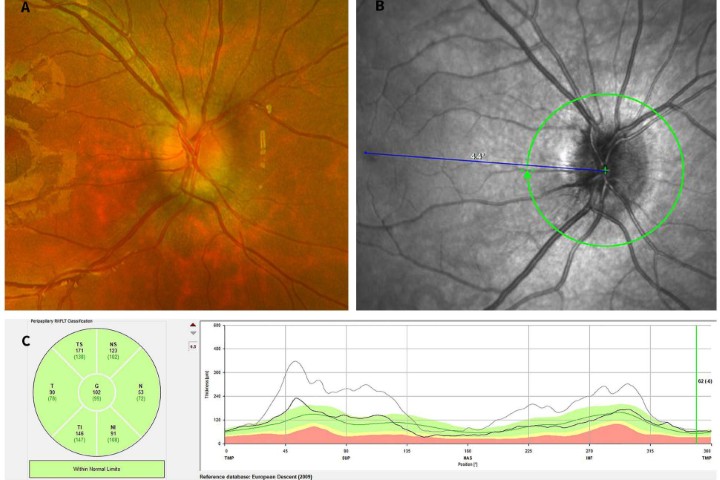

Fig.1 Anterior non-necrotising scleritis

Anterior scleritis typically presents as a painful red eye. The affected vessels are large calibre from the deep episcleral plexus and don’t blanch with phenylephrine. There may be a violaceous hue – the best way to see this is to look at the patient under natural light. Inflammation in scleritis may be sectoral, diffuse or nodular.

Always check carefully for necrotising scleritis as this can be subtle in the early stages. If in doubt, it can be useful to look with a green light and also to check for fluorescein staining over the conjunctiva.